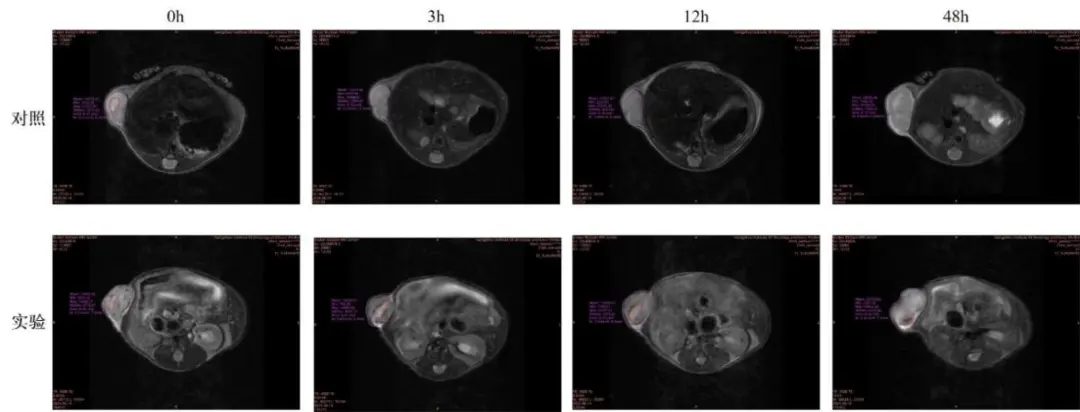

荷瘤小鼠:

T2WI肿瘤呈高信号(坏死区更亮),T1WI呈中低信号;